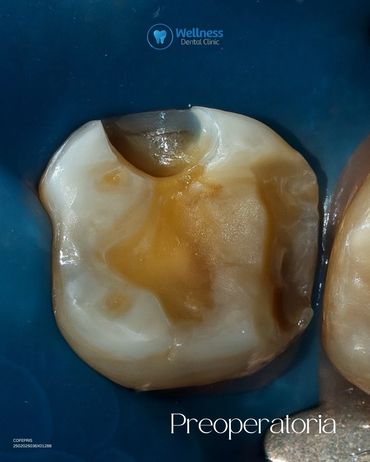

En Wellness Dental Clinic utilizamos tecnología de última generación para ofrecer restauraciones precisas, estéticas y duraderas. 🦷💙 Este procedimiento se realizó en un solo día, con una duración aproximada de dos horas. 🔹 Proceso realizado: 1. Preoperatoria – Evaluación inicial de la pieza. 2. Preparación – Eliminación de caries y conformación del diente. 3. Diseño digital en CEREC – Modelado personalizado de la incrustación. 4. Fresado – Fabricación de la restauración en cerámica de alta resistencia. 5. Prueba y ajuste – Revisión de puntos de contacto y adaptación. 6. Cementado – Colocación definitiva. 7. Pulido final – Integración estética y natural. 8. Resultado final – Función y estética recuperadas. Cada paso fue realizado bajo protocolos de precisión y seguridad, logrando un resultado completamente personalizado para nuestro paciente. ✨ 📲 Agenda tu valoración y descubre la experiencia Wellness. 📍 Independencia #1118 – Local 12, Piso 4, Zona Urbana Río Tijuana 📞 664 208 9300 | 📱 WhatsApp: 664 477 4313 🌐 wellnessdentalclinic.us 📧 wellnessdentalclinictj@gmail.com